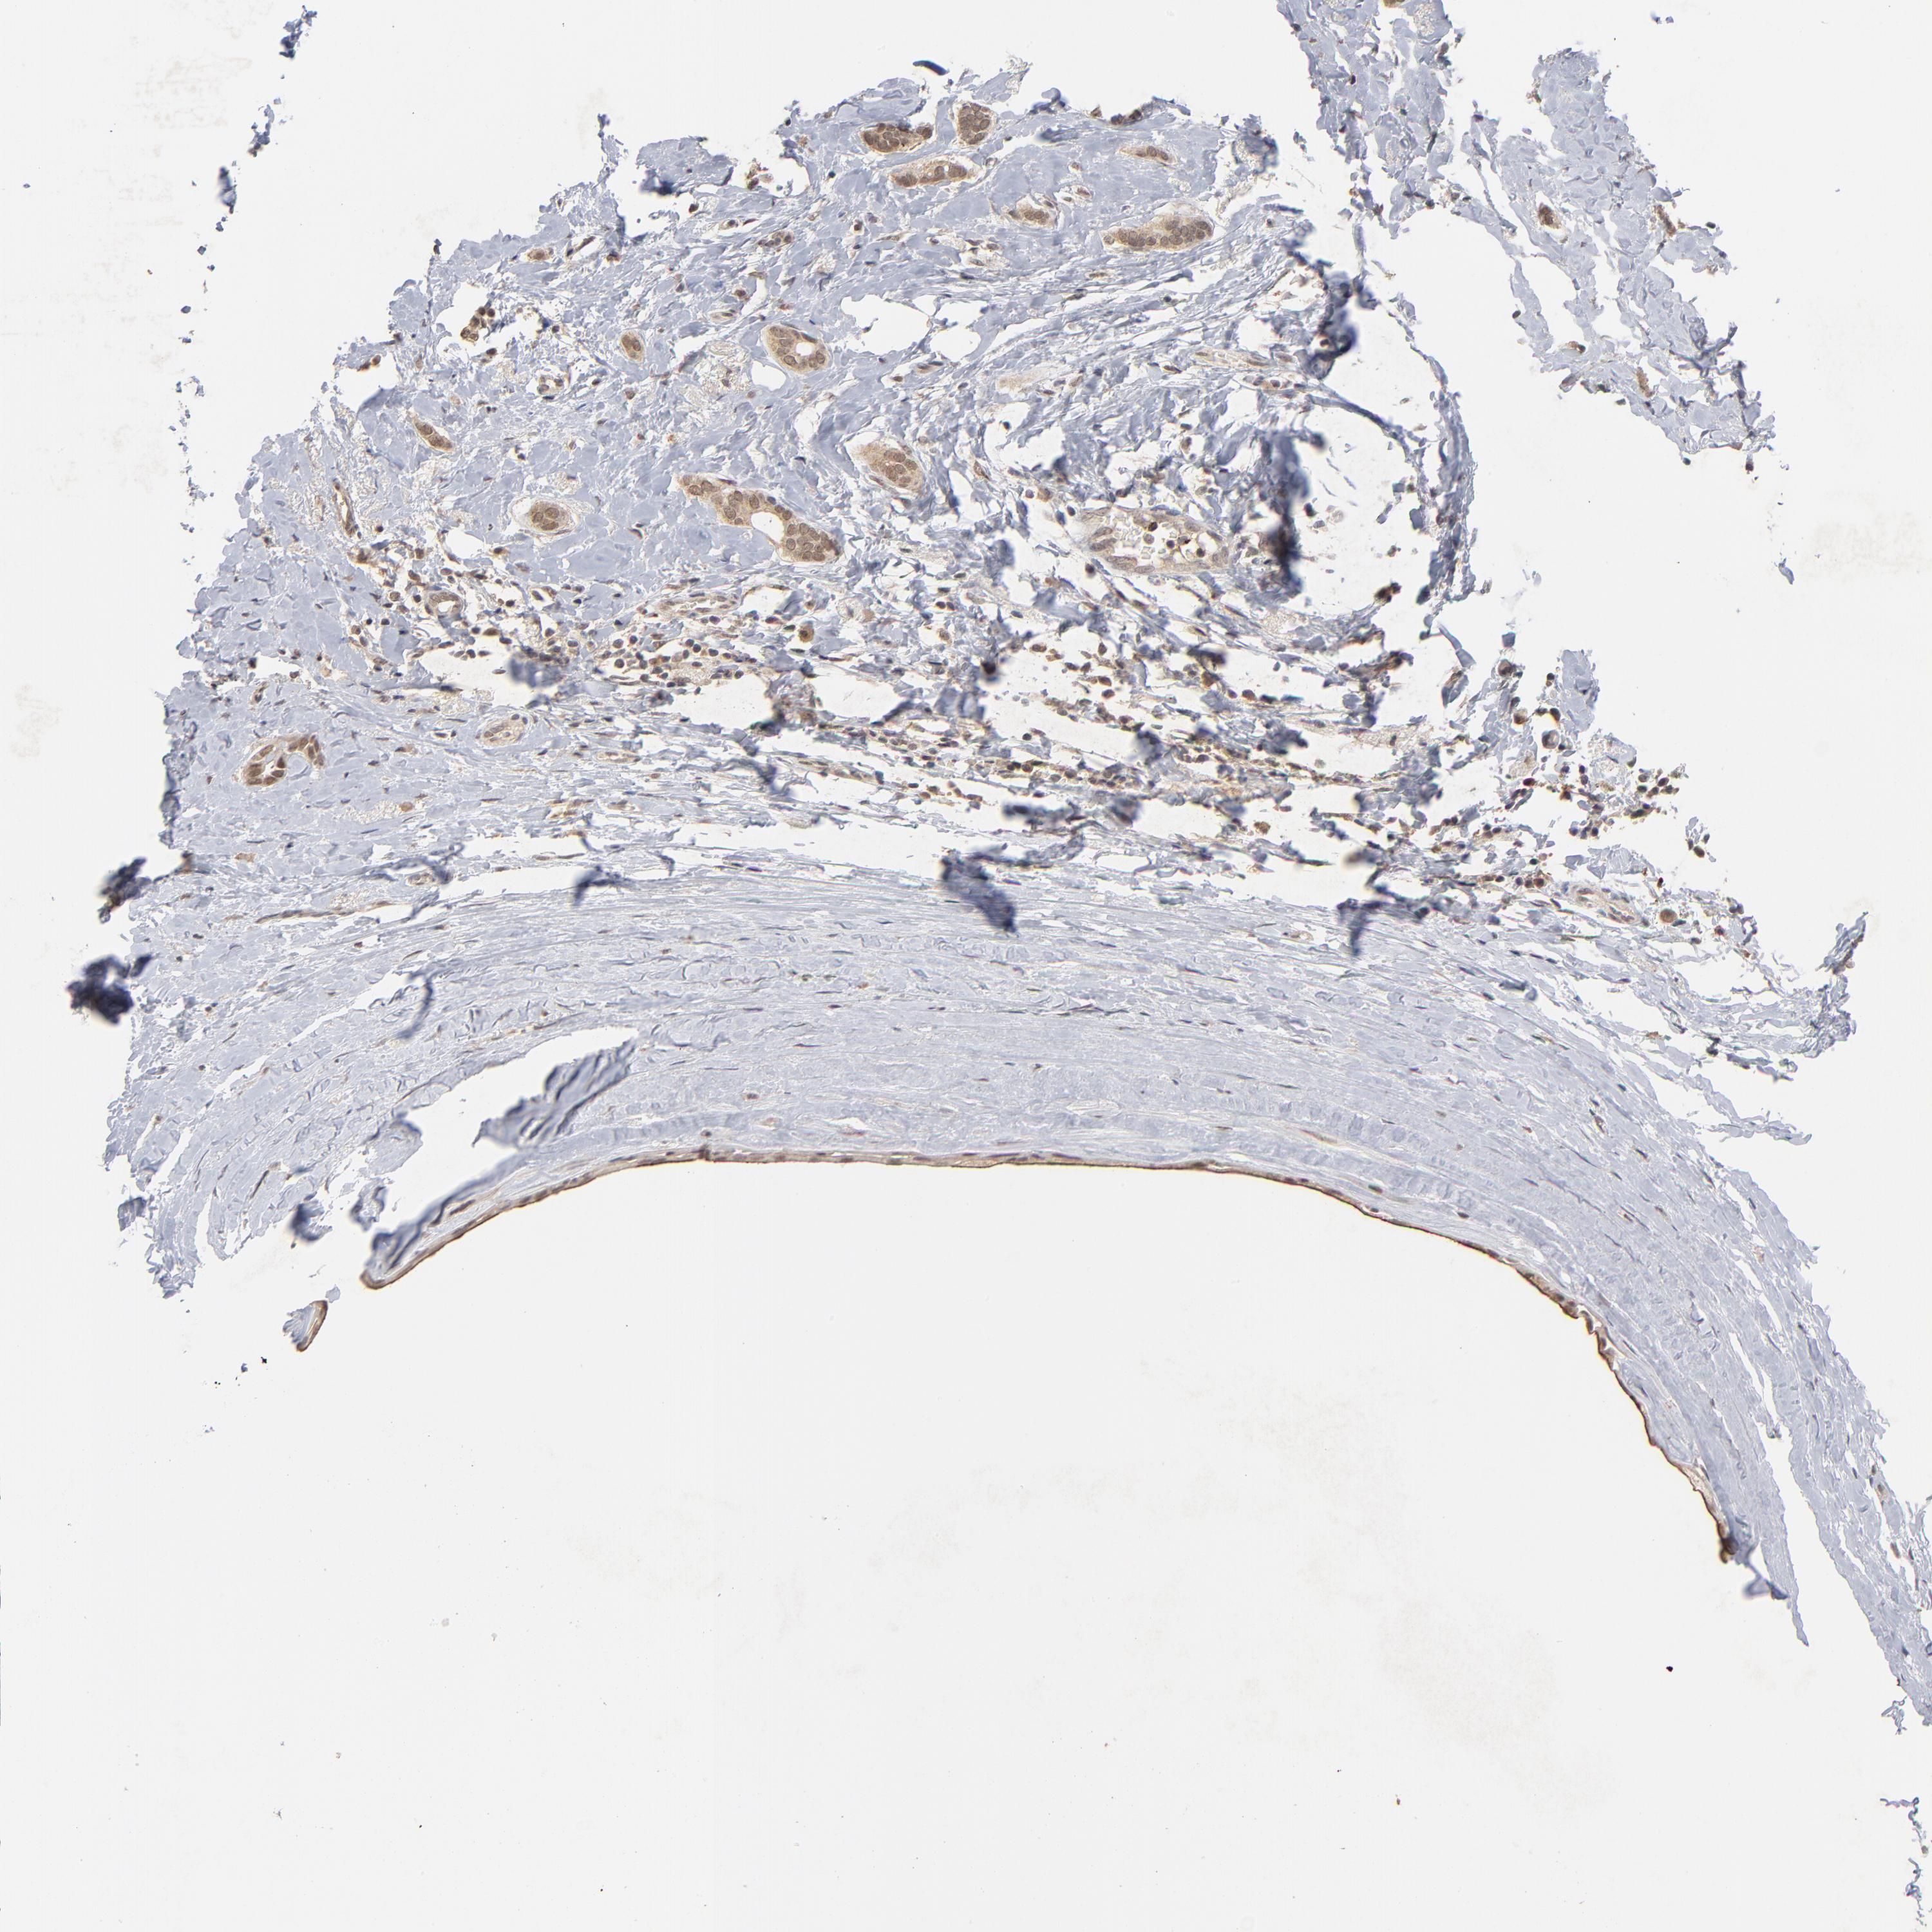

BRCA TCGA BRCA VALIDATION PROTEIN EXPRESSION

ANTIBODIES

AND

VALIDATION